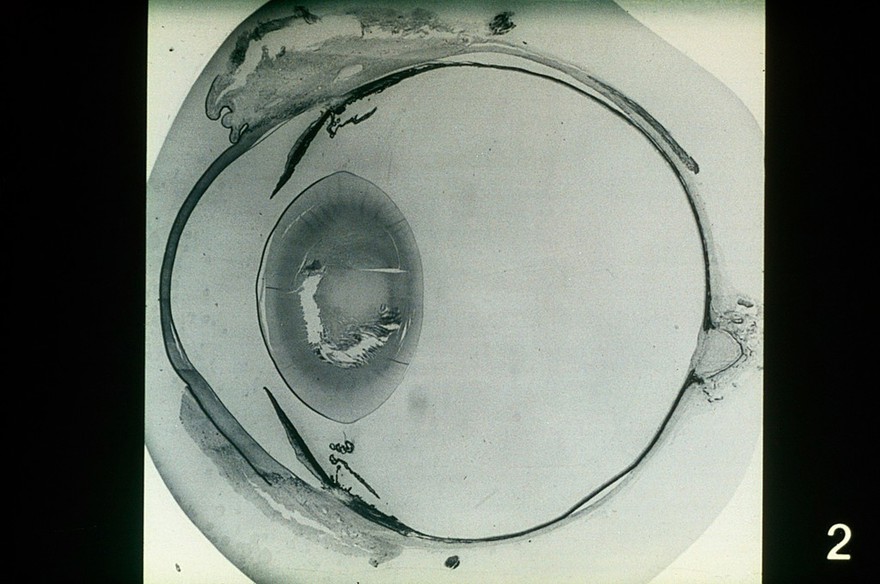

Canine eye: saggital section

P Bedford/RVC